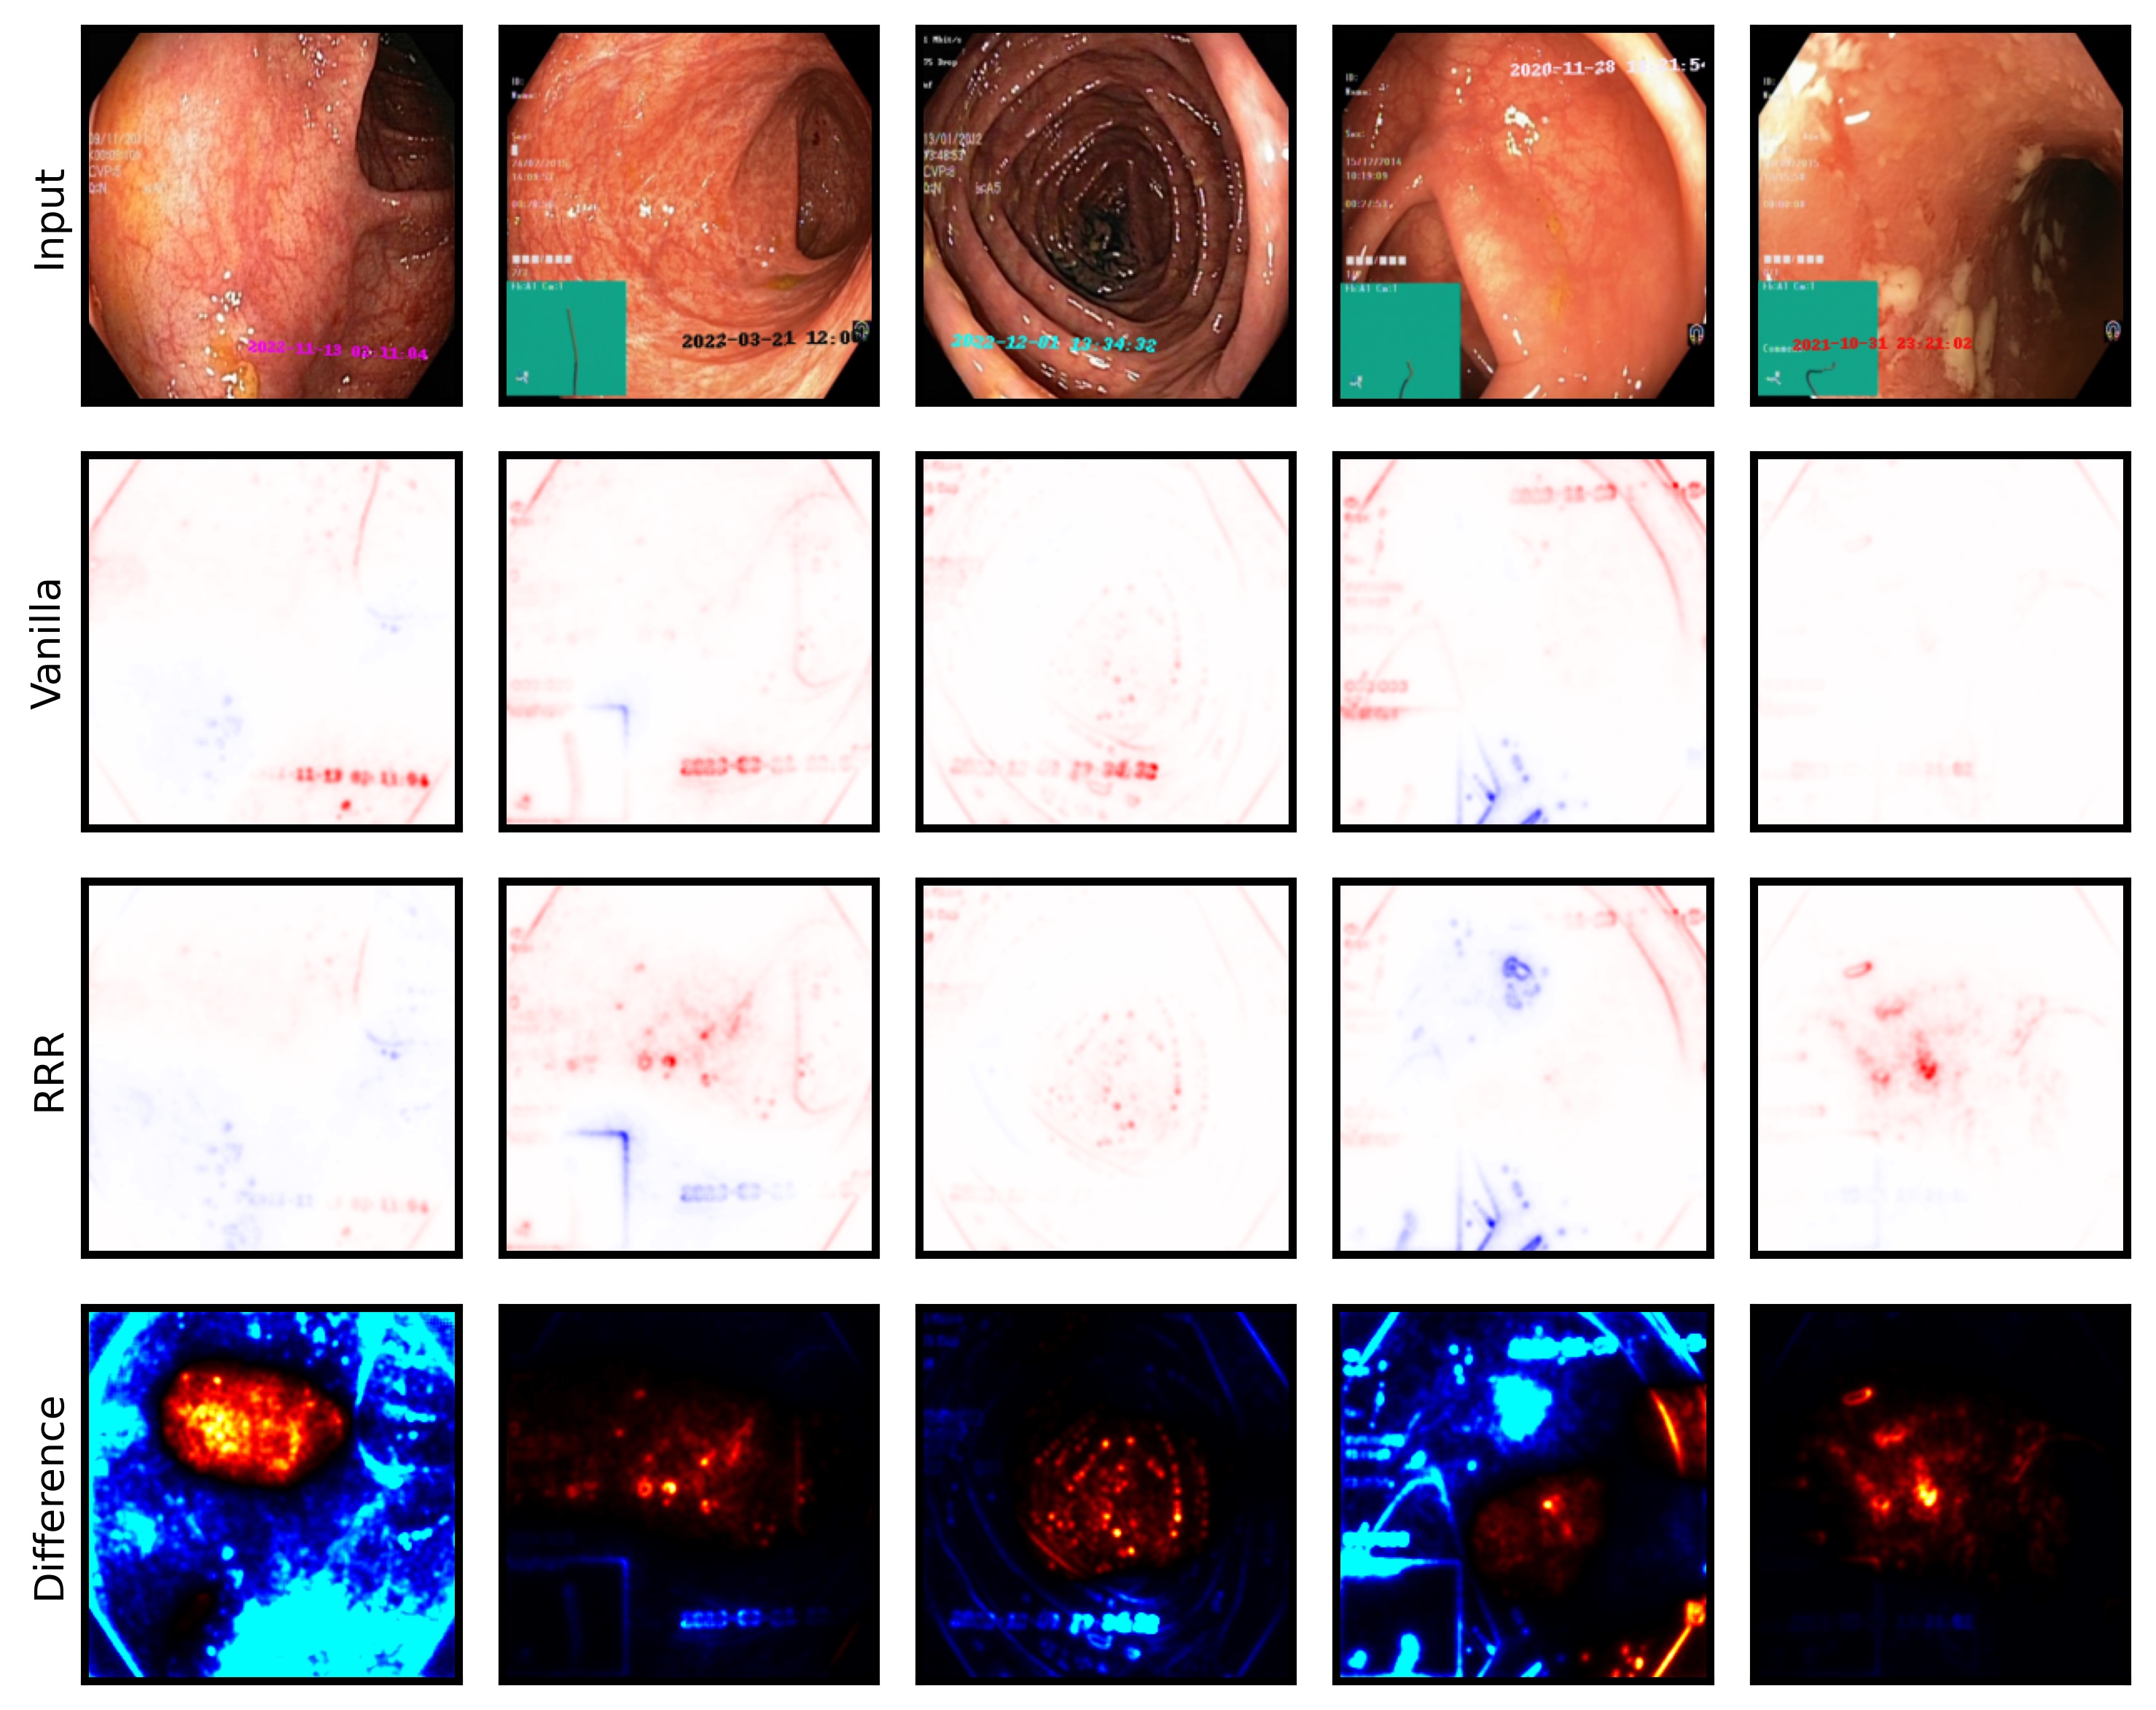

The considered datasets include ISIC2019 for melanoma detection [19, 70, 20], HyperKvasir for the identification of gastrointestinal abnormalities [10], CheXpert with chest radiographs [46], and the PTB-XL dataset [73] with 12-lead ECG (time series) data. All vision datasets contain real-world artifacts that DNNs may utilize as spurious correlation, i.e., features unrelated to the task, yet correlating with the target label. ISIC2019 is particularly known for various artifacts like colorful band-aids near benign lesions and rulers or skin markers beside malignant lesions [62, 3, 18, 59]. Moreover, HyperKvasir contains insertion tubes predominantly in samples without abnormal conditions, while CheXpert samples with cardiomegaly contain pacemakers in radiographs more frequently than in healthy patients [75]. In addition, we insert controlled artifacts into a subset of images from exactly one class per dataset. Specifically, we insert a microscope-like artifact into melanoma samples in ISIC2019. Moreover, following Dreyer et al. [28], we insert a timestamp into disease-samples from HyperKvasir, mimicking timestamps added by scanning devices. For CheXpert, we increase the brightness of radiographs with cardiomegaly, while for PTB-XL, we insert a static noise into the first second of one lead for samples with left ventricular hypertrophy (LVH). Inserting these artifacts into of samples from exactly one class creates spurious correlations for that class. Further dataset details are provided in Appendix A.4 and examples of the artifacts are shown in Fig. 5.

6.4 Spatial Bias Localization

To spatially localize biases in input space with CAVs, we compute local explanations for the element-wise product of latent activations and concept direction (see Eq. 2). We use the controlled artifacts, specifically timestamp (HyperKvasir) and micropscope (ISIC2019) with ground truth concept localization masks for evaluation. We compute (1) the percentage of relevance within the ground truth mask and (2) the Jaccard index, or Intersection over Union (IoU), of the binarized localization mask with the ground truth. In Fig. 9, we report both metrics using CAVs computed on different layers of VGG16 and ResNet50. The layer choice for concept representations is key, as for example middle layers perform better to localize timestamps and earlier layers are more effective to localize the microscope. In comparison with Fig.7, we find that the optimal layer for bias localization may differ from the one for sample retrieval. Interestingly, the IoU for the microscope artifact is consistently low, as models primarily focus on the border of the circle instead of the entire area, as indicated by qualitative results in Appendix A.6.3. Unlike artifact relevance, the IoU metric also measures how much of the expected areas the computed mask does not cover.

6.5 Bias Mitigation

We unlearn detected biases using the methods summarized in Sec. 5. We utilize RRR as input-gradient-based bias mitigation approach for localizable artifacts and the ClArC framework for all artifacts, representing biases in latent space with CAVs. Specifically, we consider the penalty-based approach RR-ClArC and the training-free model editing methods P-ClArC and rP-ClArC. To measure the bias mitigation effect, we compute several metrics inspired by prior work [59]. First, we compare the accuracy on a clean (bias-free) and a biased test set, where the bias is artificially inserted into samples from all classes. Models impacted by spurious correlations are expected to perform poorly on the biased test set. In addition, we measure the model’s sensitivity towards the bias concept by computing (1) the percentage of relevance, measured via LRP, on the artifact region using ground truth masks, and (2) the TCAV score [47]. The latter is reported as , where 0 indicates no sensitivity and higher values reliance on the artifact. Low scores are preferred after bias mitigation. The results are compared to a Vanilla model that is finetuned without a bias mitigation loss term. In Tab. 1, we report results for ResNet50 models in the controlled settings with ISIC2019, HyperKvasir, and CheXpert. For RRR, we use ground truth bias localization masks and refrain from reporting results for CheXpert, as we consider the brightness artifact unlocalizable in input space. The results confirm that all models initially rely on the spurious correlation, indicated by a large gap between clean and biased accuracies for Vanilla models. All bias mitigation approaches improve the accuracy on the biased test set while maintaining high accuracy on the clean test set, demonstrating reduced reliance on the targeted biases. This is supported by decreased artifact relevance and . Qualitative results visualizing the decrease in artifact reliance with input relevance heatmaps and additional quantitative results for other model architectures and ECG data are provided in Appendix A.6.4.